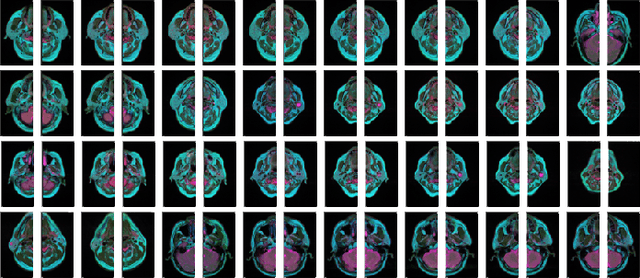

Abstract:Parotid gland tumors account for approximately 2% to 10% of head and neck tumors. Preoperative tumor localization, differential diagnosis, and subsequent selection of appropriate treatment for parotid gland tumors is critical. However, the relative rarity of these tumors and the highly dispersed tissue types have left an unmet need for a subtle differential diagnosis of such neoplastic lesions based on preoperative radiomics. Recently, deep learning methods have developed rapidly, especially Transformer beats the traditional convolutional neural network in computer vision. Many new Transformer-based networks have been proposed for computer vision tasks. In this study, multicenter multimodal parotid gland MRI images were collected. The Swin-Unet which was based on Transformer was used. MRI images of STIR, T1 and T2 modalities were combined into a three-channel data to train the network. We achieved segmentation of the region of interest for parotid gland and tumor. The DSC of the model on the test set was 88.63%, MPA was 99.31%, MIoU was 83.99%, and HD was 3.04. Then a series of comparison experiments were designed in this paper to further validate the segmentation performance of the algorithm.

Abstract:Recent works on Multimodal 3D Computer-aided diagnosis have demonstrated that obtaining a competitive automatic diagnosis model when a 3D convolution neural network (CNN) brings more parameters and medical images are scarce remains nontrivial and challenging. Considering both consistencies of regions of interest in multimodal images and diagnostic accuracy, we propose a novel mutual attention-based hybrid dimensional network for MultiModal 3D medical image classification (MMNet). The hybrid dimensional network integrates 2D CNN with 3D convolution modules to generate deeper and more informative feature maps, and reduce the training complexity of 3D fusion. Besides, the pre-trained model of ImageNet can be used in 2D CNN, which improves the performance of the model. The stereoscopic attention is focused on building rich contextual interdependencies of the region in 3D medical images. To improve the regional correlation of pathological tissues in multimodal medical images, we further design a mutual attention framework in the network to build the region-wise consistency in similar stereoscopic regions of different image modalities, providing an implicit manner to instruct the network to focus on pathological tissues. MMNet outperforms many previous solutions and achieves results competitive to the state-of-the-art on three multimodal imaging datasets, i.e., Parotid Gland Tumor (PGT) dataset, the MRNet dataset, and the PROSTATEx dataset, and its advantages are validated by extensive experiments.